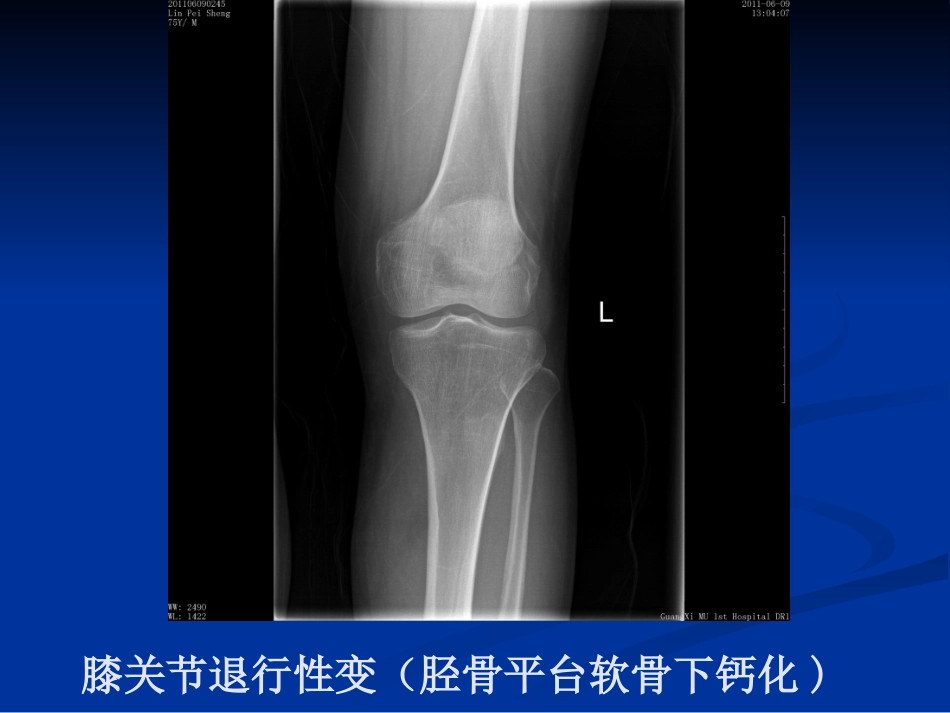

膝关节骨性关节炎昌吉州中医院针灸科昌吉州中医院针灸科孙存海孙存海膝关节退行性变(胫骨平台软骨下钙化)膝关节退行性变(骨赘形成)膝关节退行性变(半月板钙化、膝关节变形)在膝骨性关节炎的初期,由于大部分症状多为隐匿性,即使疼痛也是比较轻微或时好时坏,因此大部分病人并不在意。而恰在此时,由于一些不当的生活方式或工作习惯常常导致本病的进一步发展。到了膝关节骨性关节炎病变的中晚期,疼痛和关节活动受限常常严重影响骨性关节炎患者的日常生活和工作,有时甚至连走路这样简单的活动也会觉得非常困难。由于骨性关节炎的病程是逐渐进展的,关节疼痛和僵硬会随着时间的延长而加重,加之大部分患者对相关的医学知识了解有限,不能采取及时得当的治疗及预防措施,更容易使患者的病情进一步加重,从而...